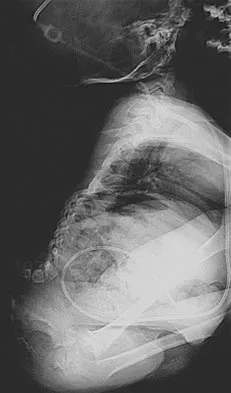

A 33-year-old woman sustains a C6 burst fracture diving into a swimming pool, resulting in a complete spinal cord injury. The canal compromise is shown in Figures 8a and 8b. Functional recovery would be maximized with

Explanation